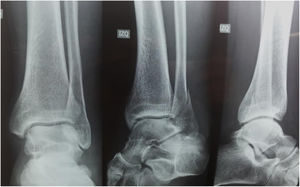

En el caso 3 se estableció como criterio quirúrgico 1mm de discrepancia de la línea de shenton y una apertura de el espacio claro medial de 6mm, además de una malrotacion del peroné y discrepancia de el ángulo talocrural, como se observo en las figuras 6 y 7. figura 8, figura 9

En momentos diferentes, se entregó a cada participante del estudio una serie con los cuatro casos, todos evaluados mediante una serie de trauma unilateral y nuevamente, pero en un momento diferente de tiempo, los mismos cuatro casos con las mediciones radiológicas explícitamente escritas y realizadas debidamente con comparación del lado contralateral sin decirle al participante que eran los mismos cuatro casos iniciales de las series de trauma unilateral.

Denominamos grupo de estudio a la serie radiográfica unilateral sin mediciones radiológicas, y grupo autocontrol a la serie radiográfica comparativa con mediciones explícitas de los mismos 4 casos de fracturas, no se alteró el orden de los casos en la encuesta.